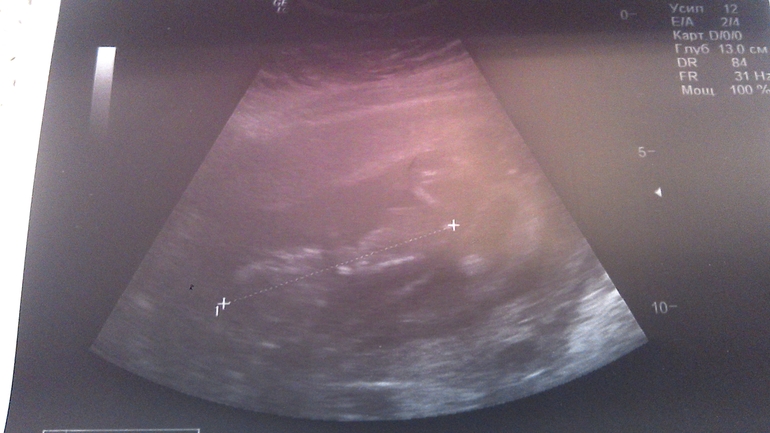

УЗИ 13-я неделя

Всё о нашей беременностиВчера разболелся живот, был тонус. появились светло желтые выделения. Позвонила врачу, она сказала такое бывает, если нет зуда не волноваться. Пить ношпу и вставлять папаверин. Сегодня проснулась и чувствую себя хорошо. Не выдержала пошла на УЗИ в Инвитро. Все хорошо, мы растем! Уже по 7 см, вертимся. Лежим в разных плодных яичках, но головка к головке. Наверное общаются))))) попробовали рассмотреть пол, хоть я и так знаю кто. Тот что по передней стенке вроде мальчик, но не точно.

Сегодня фото не очень, но запощу